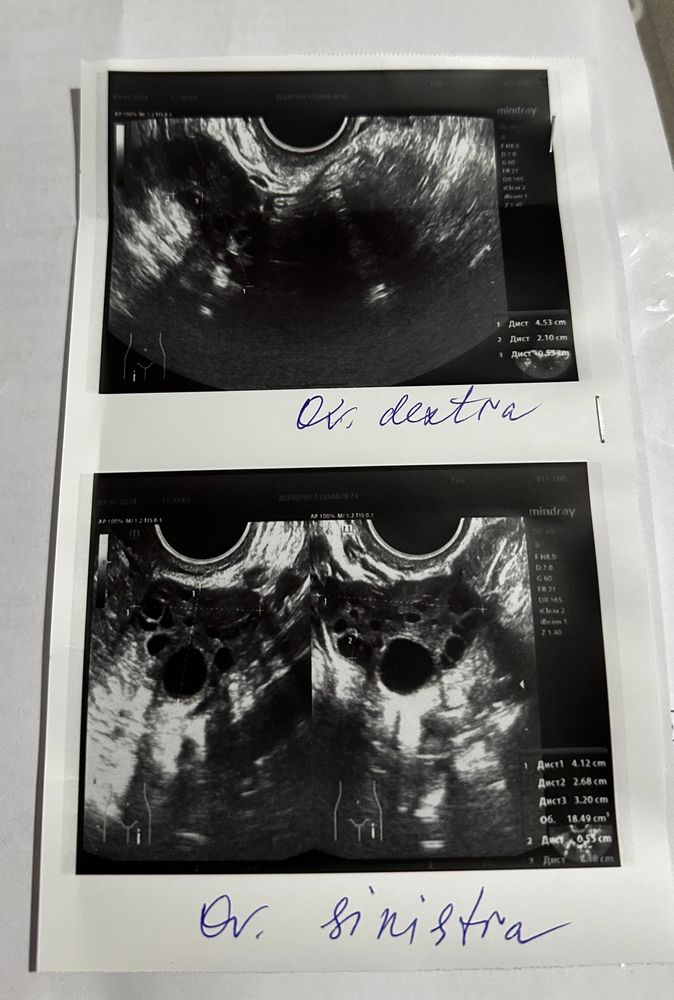

Всем привет, может кто-то умеет читать узи, к врачу запись еще не скоро, узистка толком ничего не сказала, только лишь о МФЯ, но это для меня не открытие, вопрос был о том скоро ли ждать месячные, ответа не получила, задержка 11 дней, что для меня не свойственно, с овуляцией тоже проблем как таковых не было, в этом месяце не отслеживала, возможно ее не было и из-за этого задержка

В протоколе не написано ничего про желтое тело, скорее всего овуляции ещё не было, есть доминантный фолликул размером 14,5 мм, т.е. О будет дня через 4, а потом от нее ещё 10-14 дней до М. Либо О не будет в этом цикле и тогда, когда будут М неизвестно.

Тесты при мфя не всегда информативны, но можете попробовать. Овуляция должна быть через 3-5 дней (фолликул растет в среднем на 2 мм в день, лопается от 18 мм +/-, у вас 14 мм сейчас), лучше перепроверить на узи, ну или ориентироваться на этот фолликул и ждать месячные где-то через 20 дней (если овуляция будет).

О у вас не было, ЖТ нет, свободной жидкости тоже. М в ановуляторных циклах наступают либо ранее 20-ти дней либо более 45-ти дней.

У вас нет ЖТ, первая фаза цикла. Когда будут месячные вам никто сказать не может в таком случае. Увеличенные яичники тоже не очень хорошо

Много фолликулов, ставят мультифолликулярные яичники...овуляции не бвло, так как нет желтого тела..жидкости тоже нет..